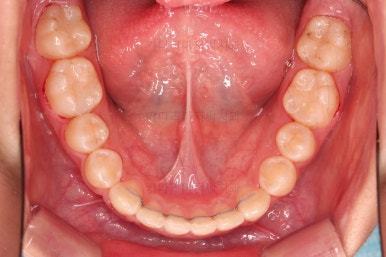

4. 마무리

종료 때의 사진입니다.

가지런하고, 교합도 좋으며 과개교합이나 앵글씨 2급 부정교합 부분도 완벽히 좋아졌습니다.

자연스럽게 중앙선도 매우 좋아졌고요.

이제 전후 비교를 해보겠습니다.

이상 삐뚤어진 치아와 부정교합을 가진 청소년 환자분을 발치나 미니스크류 없이 개선한 부산청소년교정치과 치료사례였습니다.